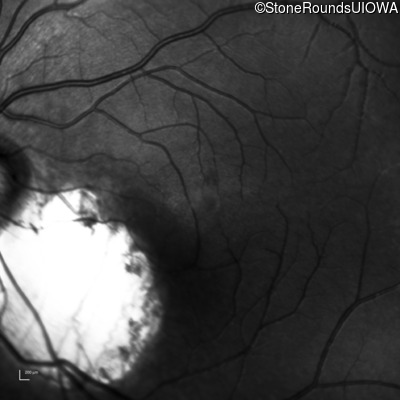

Infrared Fundus Photograph - Left - 20/50 +2

Exemplar